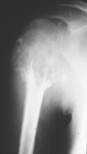

ТУБЕРКУЛЕЗНЫЙ КОКСИТ. Это обычно первично-костное заболевание - первичный туберкулезный очаг возникает чаще (64%) в костях вертлужной| впадины|. В результате|вследствие| прорыва процесса в сустав возникает разрушение суставных хрящей, синовиальной| оболочки, суставной сумки, впоследствии процесс переходит на другую кость. Возможны дистензионные| вывихи| при острых процессах, в результате|вследствие| растяжения| суставной сумки большим|великим| количеством выпота|потоотделения|; при значительных разрушениях суставных концов костей наблюдаются деструктивные вывихи. При благоприятном течении и своевременном лечении процесс может закончиться некоторой|некоей| деформацией суставных поверхностей с сохранением|сохранностью| функции сустава; при выраженных деструкциях суставных поверхностей процесс заканчивается внутривертельным| псевдоартрозом или фиброзным анкилозом, или деструктивным вывихом. Рентгеновские признаки: регионарный остеопороз, уплотнение суставной сумки, очаг деструкции в костях сустава.

Рис.14. Туберкулезный коксит.